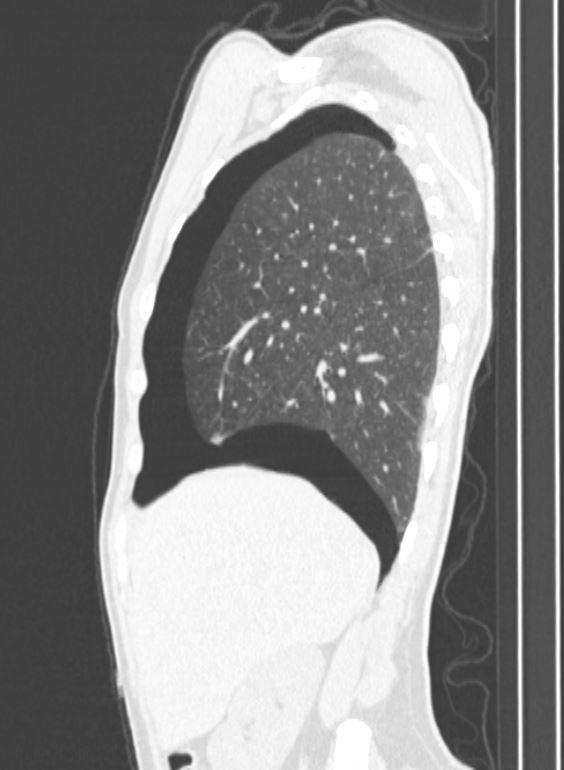

*27-year-old male with pleuritic chest pain and mild dyspnoea.

What is the most likely diagnosis?

Answer: Secondary spontaneous pneumothorax secondary to blebs